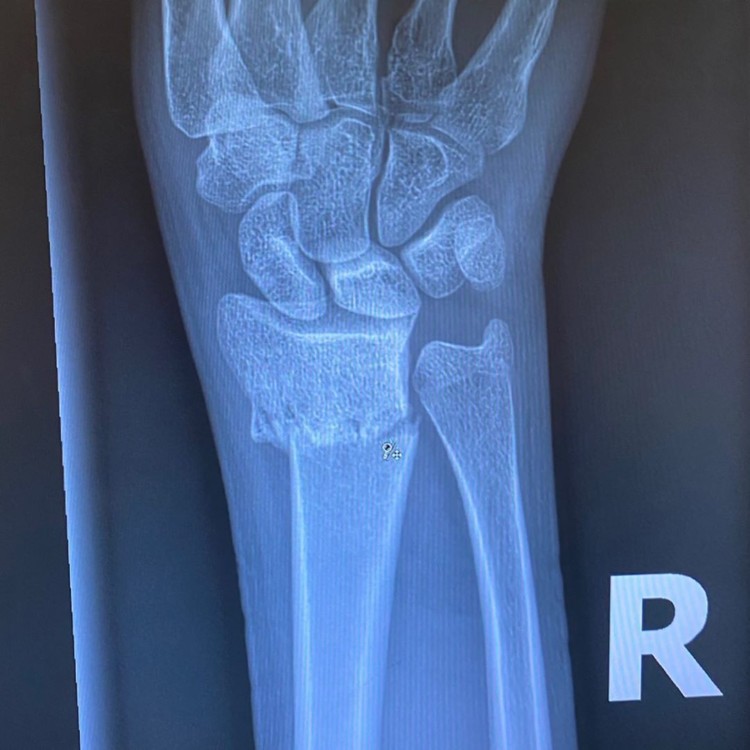

Ба більше, Кая також демонструвала рентген руки, на якому видно злам променевої кістки. На жаль, дівчина не розповіла подробиць інциденту.